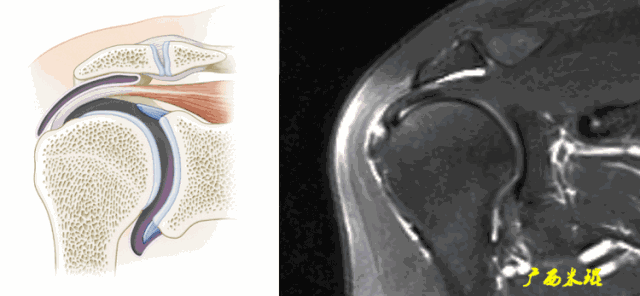

1、信号异常

肩袖出现3级信号,是诊断的直接征象,一旦发现3级信号,肩袖撕裂无疑。

a、肩袖关节侧出现3级信号,部分撕裂。

b、肩袖滑囊侧出现3级信号,属于部分撕裂。

c、肩袖内部出现大范围3级信号,属于部分撕裂。

d、肩袖出现3级信号,关节侧撕裂回缩,也属于部分撕裂。

e、肩袖出现3级信号,肩袖完全中断,属于完全撕裂但无回缩。

2、形态异常

肩袖可以变薄、变厚或不规则,但只有中断才是3级信号,肩袖中断后断端回缩,肌肉萎缩也是肩袖撕裂的直接征象。